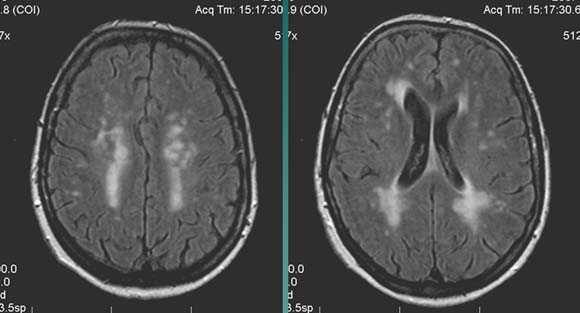

Характерным проявлением ДЭП на МР-томограммах является наличие множественных очагов глиоза.

В белом веществе левой лобной и обеих теменных долей, преимущественно субкортикально, выявлены множественные мелкие очаги хронической ишемии (большинство локализованных в бассейне правой средней мозговой артерии).

Проявлением хронической ишемии является также развитие выраженных дистрофических изменений белого вещества паравентрикулярной локализации - лейкоареоз.

Выраженные дистрофические изменения белого вещества паравентрикулярной локализации - лейкоареоз.

Сочетание мультифокальных очаговых изменений с диффузной кортикальной церебральной атрофией.